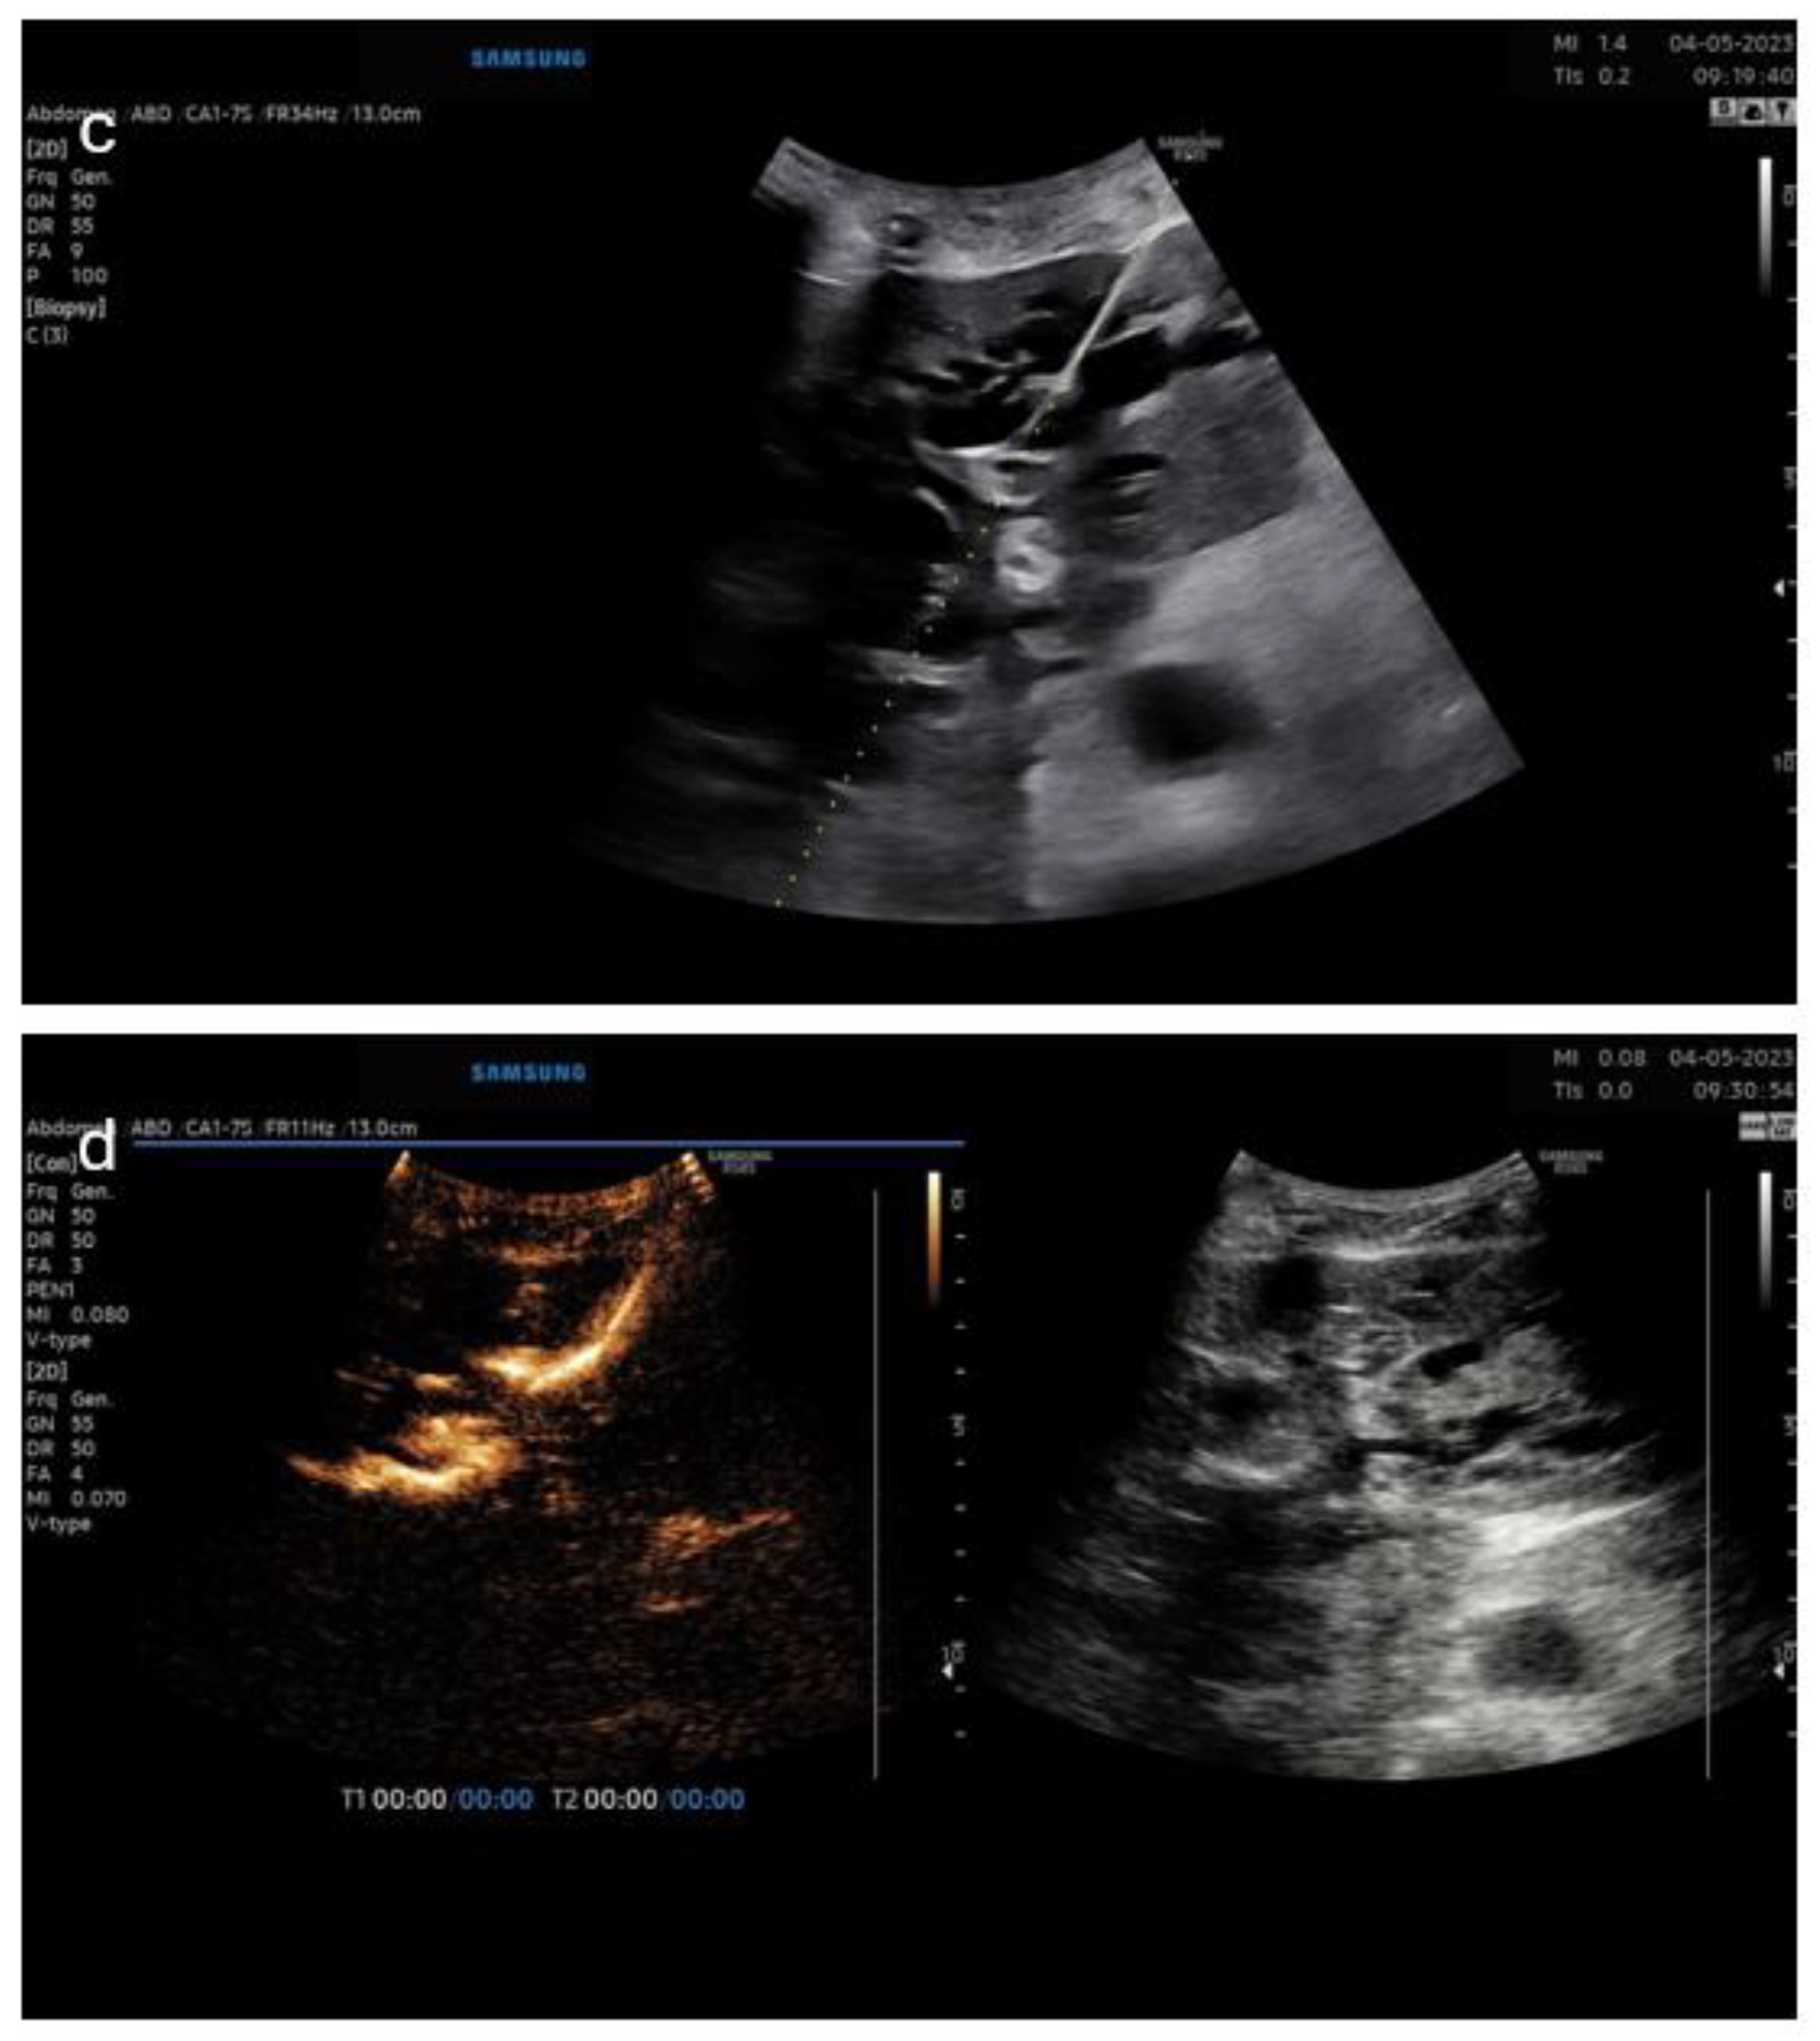

3.5. Pictorial Examples